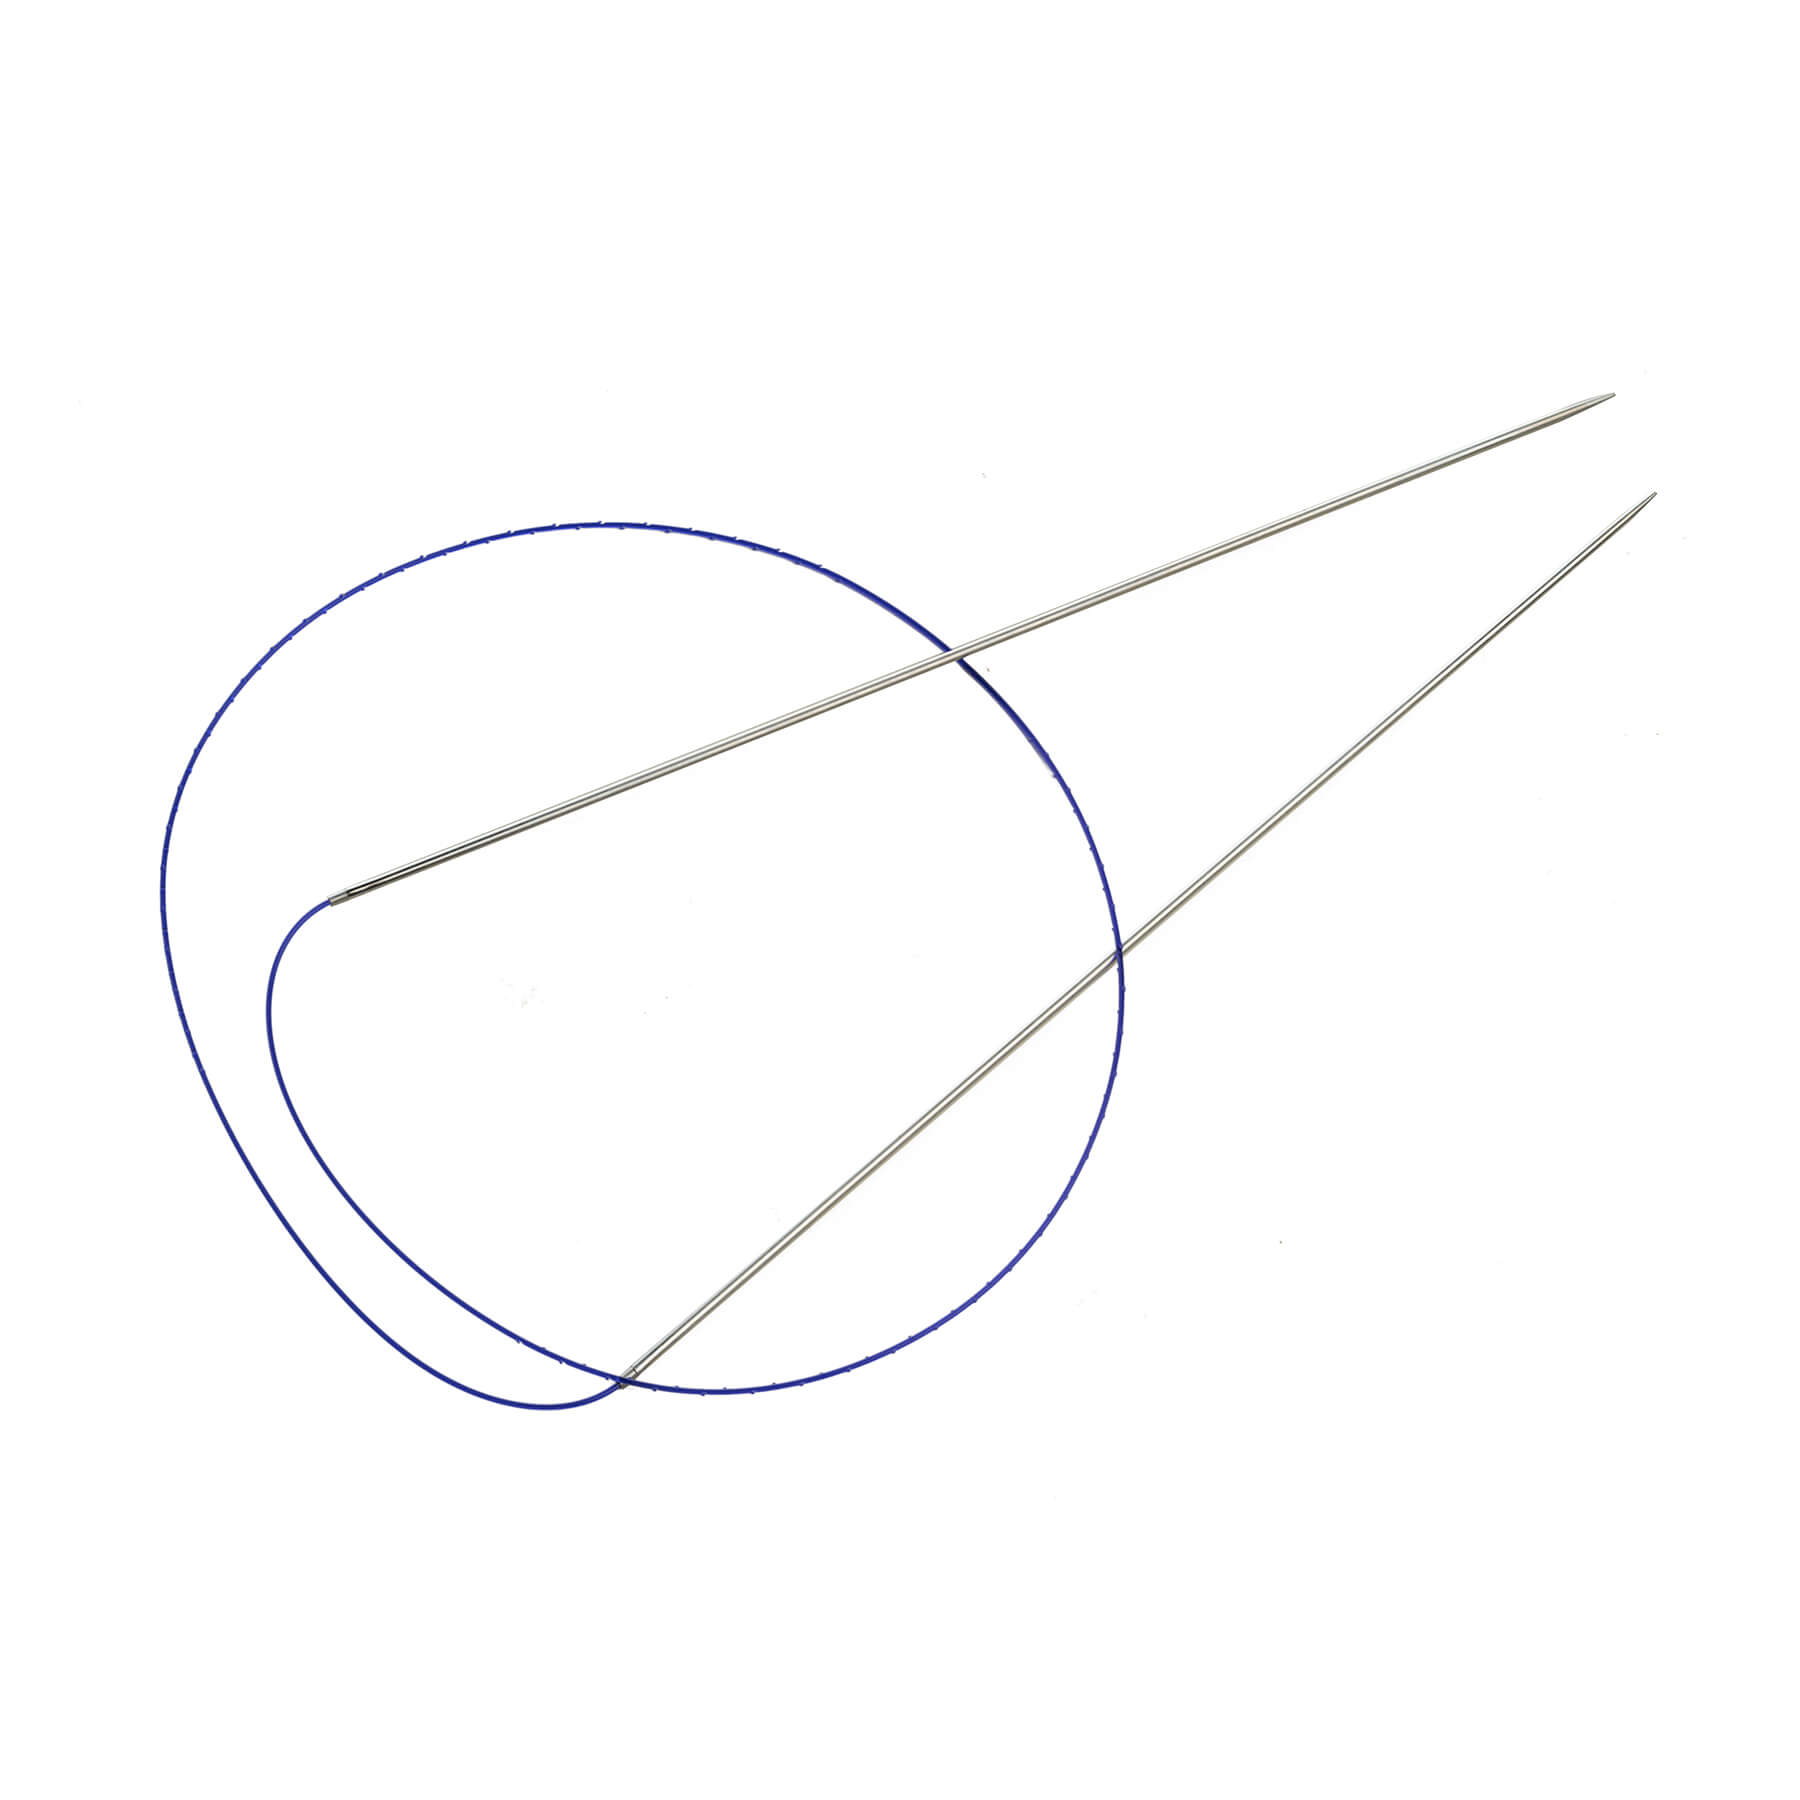

Velvet Dual Lift thread features a unique double needle for achieving a natural and immediate lifting effect in the desired area.

The thread is injected through a single injection site, which significantly reduces the damage to soft tissue.